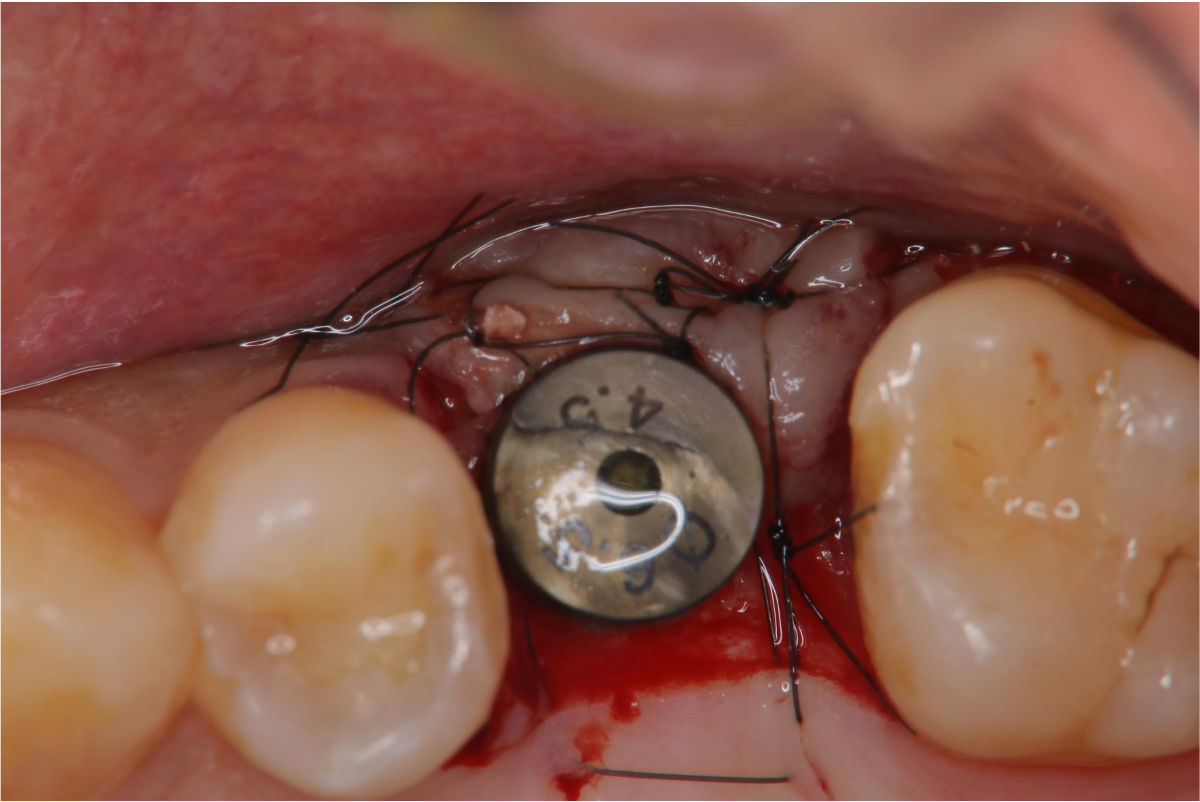

二階手術